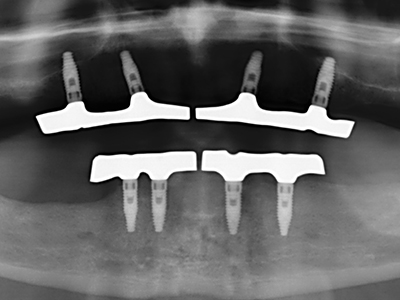

Abb. 11: Das postoperative OPTG veranschaulicht die vertikale Augmentation und Sinusbodenelevation.

Abb. 15: Die röntgenologische Ein-Jahres-Kontrolle zeigt stabile Verhältnisse des Knochenniveaus.